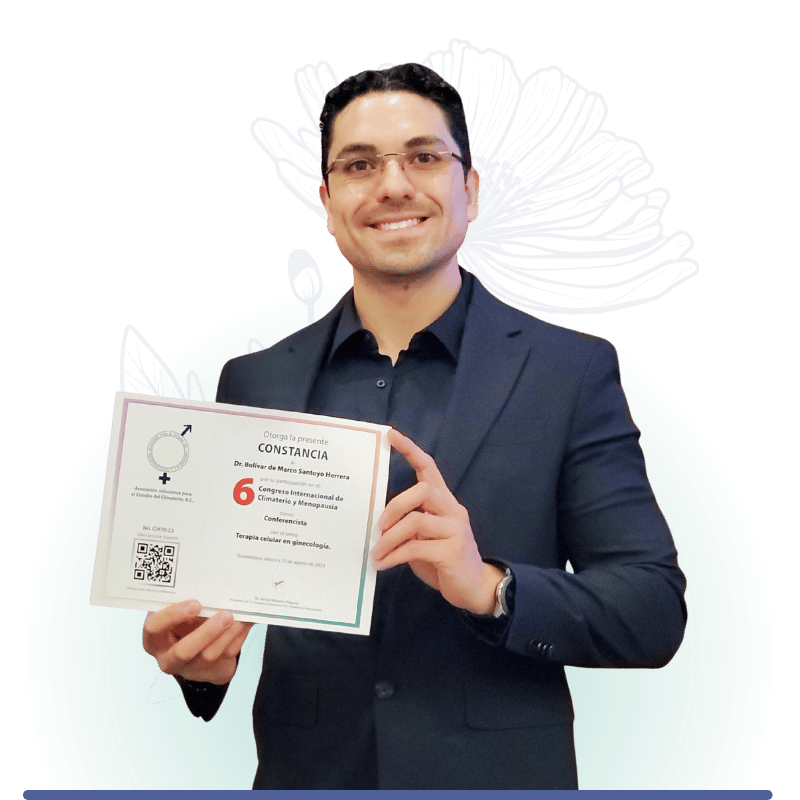

El Dr. Bolívar Santoyo es un especialista en Medicina Reproductiva reconocido por su amplia experiencia en el tratamiento de la infertilidad ...